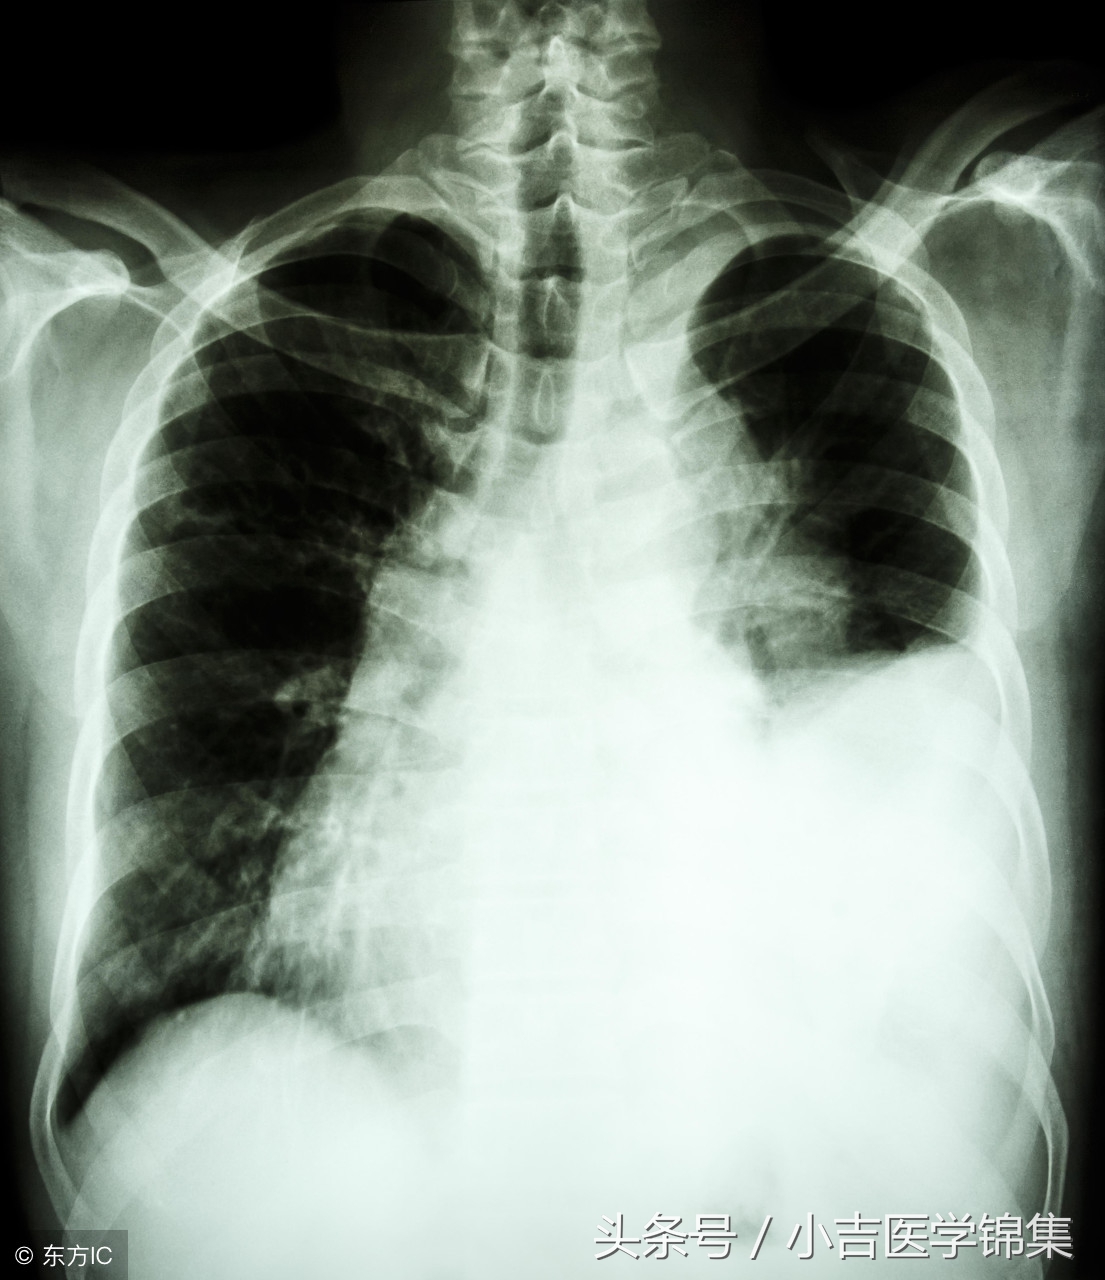

1、胸部X线:在胸片上判断胸腔积液的标准为:在第4前肋间以下为少量胸腔积液,第4前肋与第2前肋之间,属于中等量胸腔积液,积液位于第2前肋以上者,为大量胸腔积液。

⑶积液量>500ml,表现为凹面向上,外侧高内侧低的弧形积液影。

⑷大量胸腔积液:整个患侧胸部呈致密影,纵隔和气管向健侧偏移。